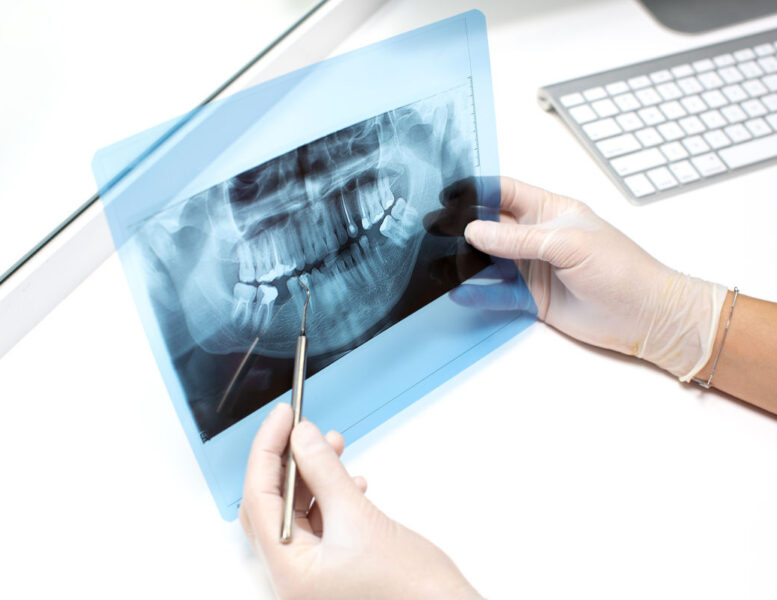

Expert Oral and Maxillofacial Surgery in Malaysia to treat diseases, injuries, and defects of the jaw, face, and oral region with precision and care.

Oral and maxillofacial surgery is a surgical specialty focusing on the diagnosis, surgical treatment, and management of diseases, injuries, and defects affecting the mouth, jaws, face, and associated structures.

At Island Hospital, our oral and maxillofacial surgery team provides specialised care for complex jaw, facial, and oral conditions. From dental clearance before major medical procedures to reconstructive and corrective surgeries, we combine advanced surgical techniques with personalised treatment plans to ensure the best possible outcomes for our patients.